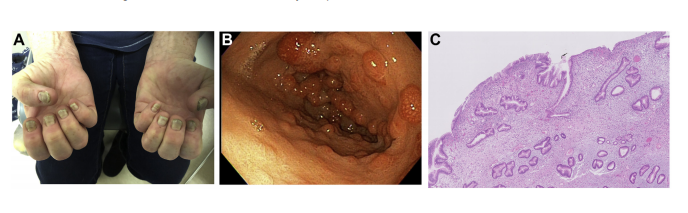

Quiz: Náuseas e diarreia com alterações nas unhas e no cabelo